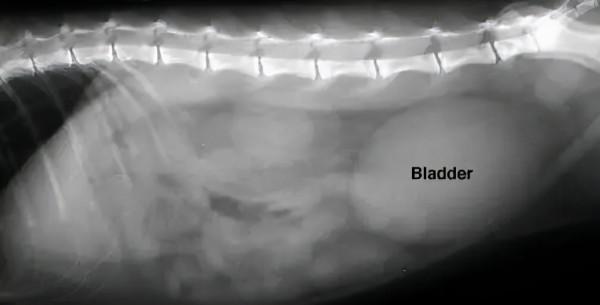

↑圖片右側的的橢圓形影像是一個充盈的膀胱

對於小貓咪來說,最重要的是儘快恢復尿道通暢。